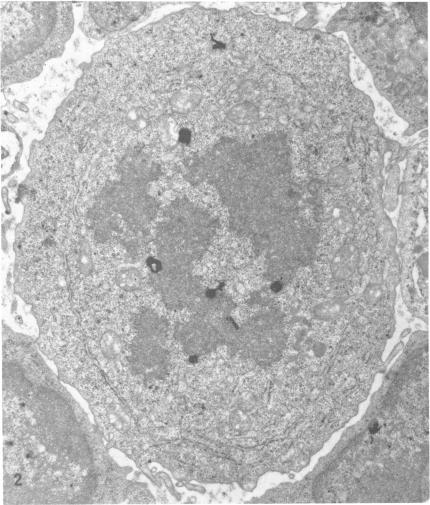

Cellular events during the expression of immunologic memory.

A series of experiments were designed to identify cytologically the cell endowed with immunologic memory and to depict morphologically the cellular events that occurred during the anamnestic response. With the use of radioactive labels and autoradiography at the light and electron microscopic levels, the concatenated phenomena from activation of memory cells to production of antibody could be followed. The memory cell was found to be a lymphocyte which, when activated by specific antigen, enlarged and transformed into either a blast cell or an immature plasma cell. Accompanying this transformation was a boost in proliferative activity of blast and immature plasma cells. This augmented mitotic activity was significantly greater than the level determined in control situations. Following the proliferation among labelled blast and immature cells, maximal labelling occurred in temporal sequence among plasma cells and large lymphocytes and finally among small lymphocytes. Antibody-forming cells were detected chiefly among lymphocytes and plasma cells and increased over the 4 days during which lymphocytes and plasma cells were differentiating from precursor immature elements. The primary response to antigen simulated in many respects the secondary response, but at a significantly lower level.